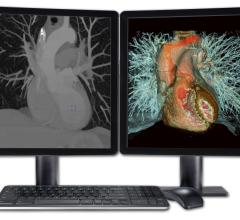

TeraRecon, a provider of medical image management solutions, debuted it’s iNteract+ solution at the 2014 Healthcare Information and Management Systems Society (HIMSS) annual conference.

VitreaView, a universal viewer developed by Vital Images Inc. was featured in a live case study. Shafiq Rab, M.D., vice president and chief information officer at Hackensack University Medical Center, presented during the Interoperability Showcase, Feb. 25 at HIMSS 2014 in Orlando, Fla.

Fovia, Inc. and Visual Medica announced a collaboration to deliver innovative, cost-effective advanced visualization to the Latin American market.

At HIMSS 2014, Sectra exhibited updates in PACS and imaging workflow. Adar Palis, executive vice president and chief operating officer of Harrison Medical Center, will present Northwest ImageShare. The collaboration between competitors that enables economies-of-scale pricing, system standardization for physicians and improved patient care was presented at HIMSS, Feb. 27.